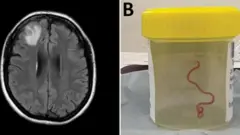

Bwa mbere ku isi inzoka nzima bayisanze mu bwonko bw’umugore wo muri Australia